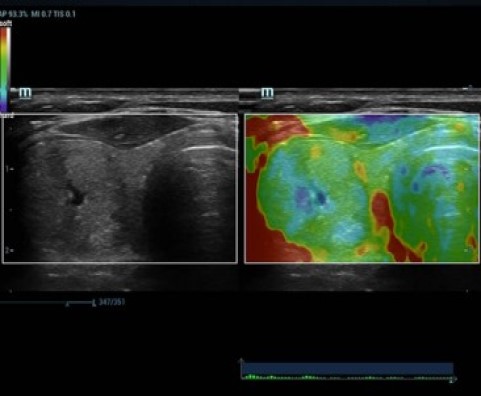

С момента основания компания Mindray непрерывно ищет новые способы повышения точности диагностики. Основанная на самой передовой технологии ZONE Sonography? новая платформа ZST+, выводит качество ультразвуковой визуализации системы Resona 7 на более высокий уровень за счет использования зонного сканирования и канальной обработки данных.

Обеспечивая качество изображения уровня премиум, Resona 7 также повышает клинические возможности исследования при помощи революционной системы V Flow, предназначенной для оценки гемодинамических показателей сосудов; обеспечивает интеллектуальное получение из 3D данных наиболее важных проекций для диагностики ЦНС плода. Сочетая в себе интуитивно понятное сенсорное управление с распознаванием жестов и все важные клинические характеристики, передовая система Resona 7 настоящая новая волна в сфере ультразвуковых инноваций.Благодаря перечисленным выше характеристикам, Resona 7 является доступным решением премиум-класса, которое удовлетворяет высоким требованиям клинической точности и эффективной диагностики в условиях современной перегруженной больничной среды.